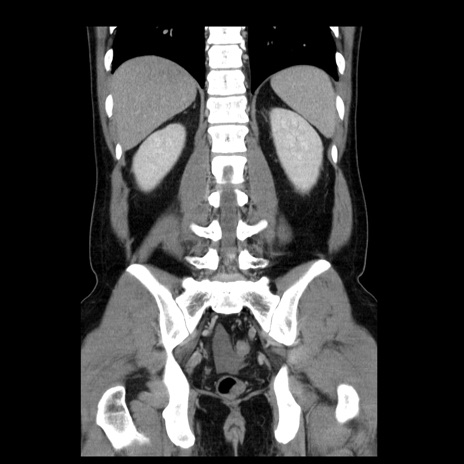

症例4(冠状断像)

【症例】30歳代男性

【主訴】腹痛、嘔吐

【現病歴】昨晩から突然の腹痛あり、その後嘔吐、軟便も出現。腹痛が改善しないため救急搬送となる。2日前にしめ鯖の食事歴あり。

【身体所見】意識清明、苦悶様、BP 135/90mmHg、BT 35.7℃、腹部:平坦、やや硬、心窩部〜臍部に自発痛、圧痛あり、筋性防御+、反跳痛-

【データ】WBC 8100、CRP 0.57